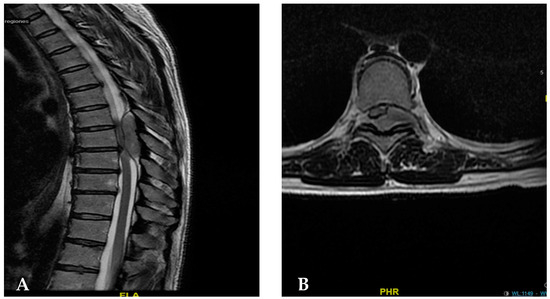

| [30] | 55/Female | T6–T8 | 2-year progressive back pain Weakness on both legs | T6–T8 laminectomy | Angiomatous meningioma | Improvement of motor weakness |